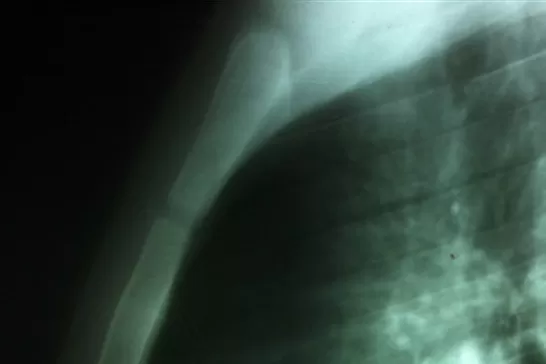

BUENOS AIRES.- Un joven de 19 años estuvo al borde de la muerte y se escapó. El lunes, recibió el disparo de una pistola neumática que manipulaba un compañero, que provocó que se le incruste un clavo en el corazón, por lo que fue intervenido de urgencia. Un equipo médico del hospital El Cruce Néstor Kirchner, de la localidad bonaerense de Florencio Varela fue el responsable de la operación que convirtió al joven en la cuarta persona en el mundo en sobrevivir a esta cirugía.

El clavo, de ocho centímetros de largo, había atravesado el esternón y el ventrículo derecho del corazón, y quedó alojado en la cavidad cardíaca. (Télam - DYN)

"En el quirófano se procedió a la apertura del hueso del esternón con mucho cuidado porque se corría el riesgo de chocar con el clavo y agrandar la herida cardíaca", explicó el médico Marcelo Nahín, quien dirigió la cirugía. "Ya con el elemento perforante a la vista realizamos la extracción manual del objeto que se había incrustado en la cara anterior del ventrículo derecho", detalló.